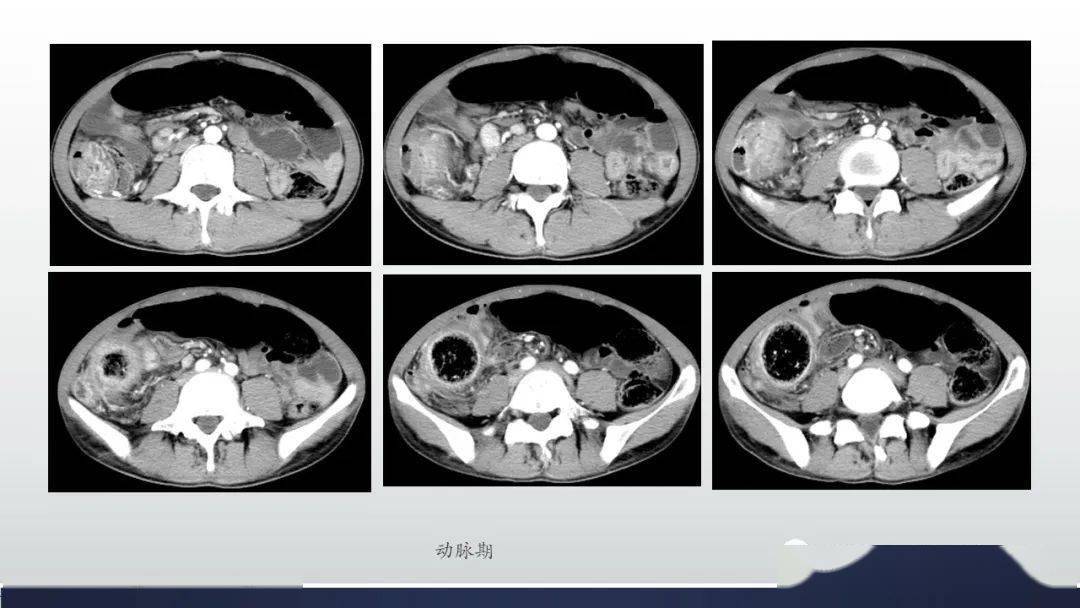

增厚的肠壁平扫,动脉期,静脉期和平衡期ct值分别是39,66,85,91 平扫